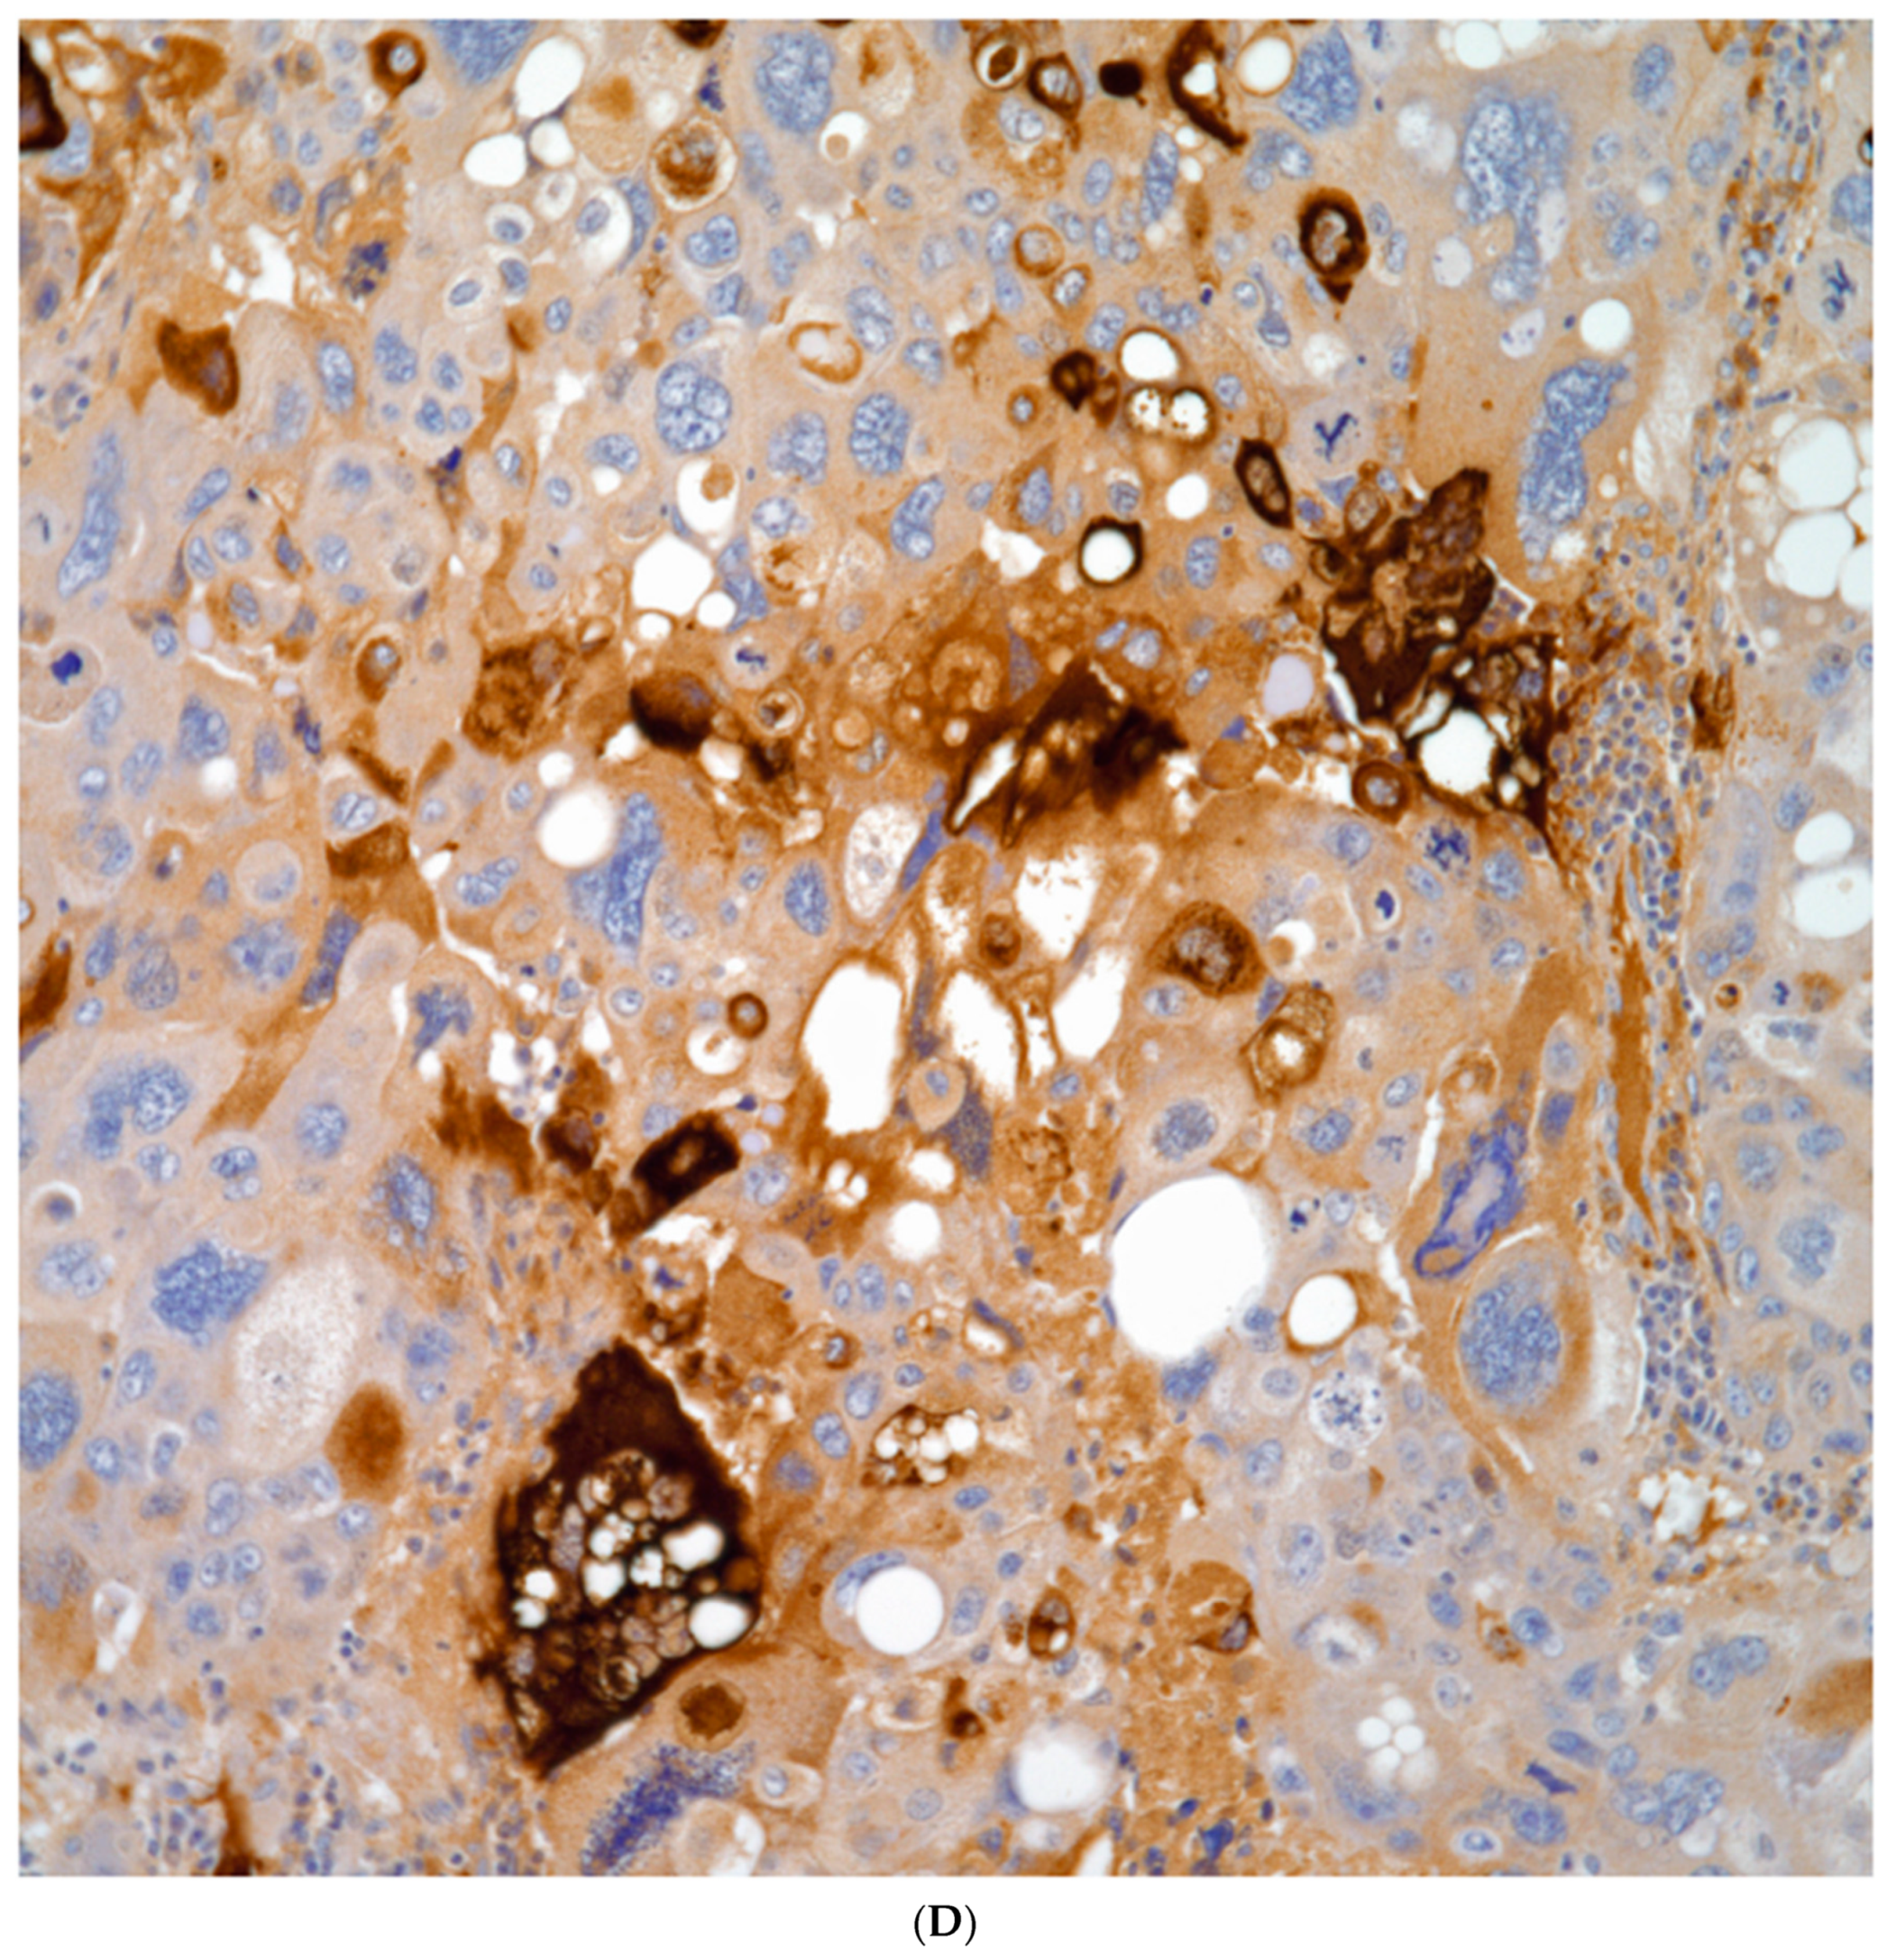

The use of the conventional pneumocytic and squamous markers such as TTF-1, Napsin A, p40, p63, and keratin 5/6 are commonly used in the evaluation of non-small cell carcinomas. These markers also play an important role in the evaluation of the spindle cell component as it has been demonstrated that the spindle cells may show positive staining for either pneumocytic or squamous markers, which will provide a more accurate classification of these tumors (Figure 8A–D). On the other hand, the use of other markers such as human chorionic gonadotrophin, cytokeratin, CD68, cathepsin, and histone H3 may provide important information in the type of giant cells present, thus a more accurate classification of these tumors.

Figure 8. A) Keratin positive in a sarcomatoid carcinoma; B) p40 positive in a sarcomatoid squamous cell carcinoma, C) TTF-1 positive in a pleomorphic carcinoma; D) HCG positive in multinucleated giant cells.